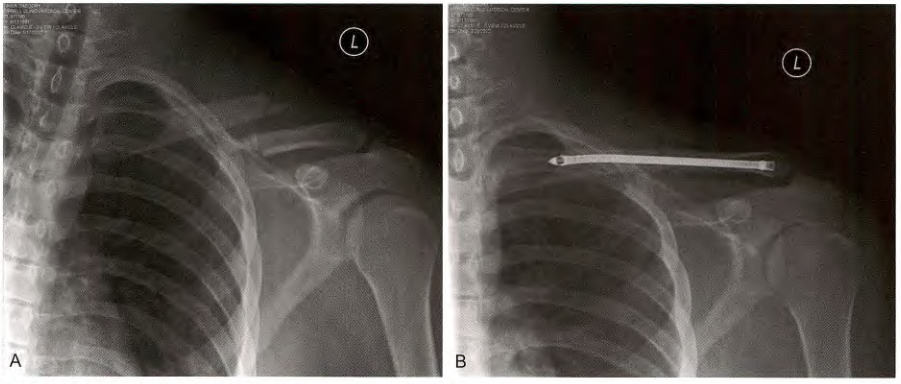

钢板和螺钉固定

A.锁骨骨折, B.前方钢板固定

双微型碎片钢板

锁骨骨折的切开复位内固定